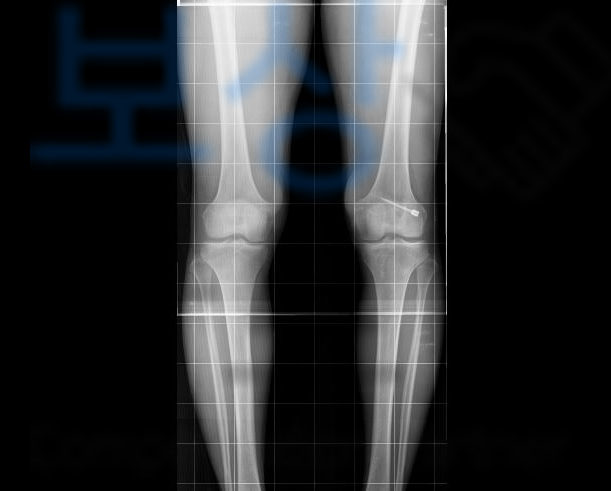

전방십자인대파열로 재건술을 받은 경우 바로 이 무릎의 흔들거림 즉 동요도를 근거로 장해를 평가합니다. 무릎의 동요관절을 평가할 때에는 건측과 환측을 비교하는데요, 바로 이 객관적 검사상 차이나는 동요도로 관절의 기능에 약간, 뚜렷한, 심한 순으로 보험금을 지급하게 되죠.

6mm 이상의 관절 동요로 약간의 장해 5% 지급율에 해당했죠. 저희는 위 후유장애진단서를 기초로 보험금 청구를 진행하였고 적정성을 증명하기 위해 의사자문 및 증빙자료도 함께 송부했습니다.